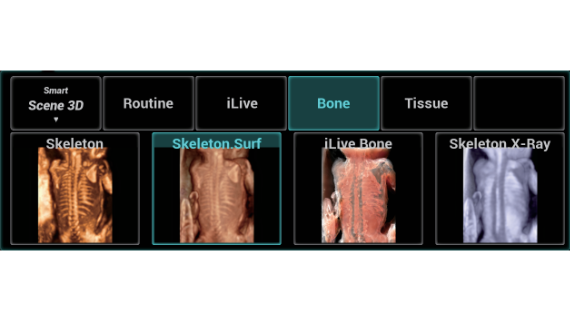

Full-stack Solution Powered by ZST?+

The ZST+ platform is an extraordinary innovation, representing an ultrasound evolution. Transforming ultrasound metrics from conventional beam-forming to channel data based processing. It overcomes the traditional trade-off limitation among spatial resolution, temporal resolution and tissue uniformity, delivering exceptional image quality for infinite imaging solutions with non-stop improvements.